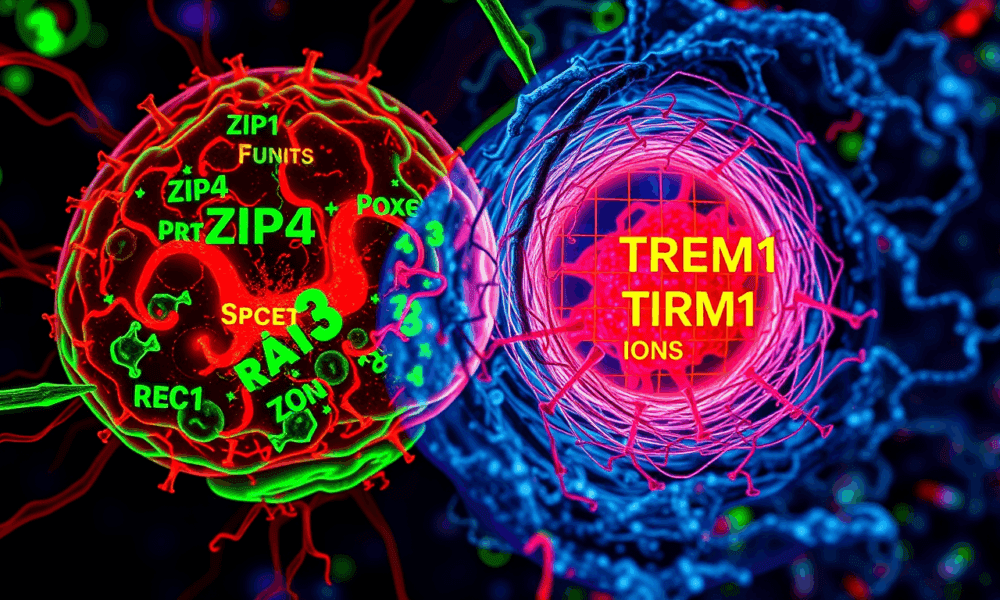

Researchers detail their discoveries about why the brain tumor glioblastoma is so aggressive. Their findings center on ZIP4, a protein that transports zinc throughout the body...